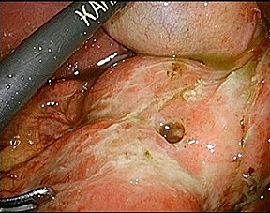

[十二指腸潰瘍穿孔] 手術:腹腔鏡下胃・十二指腸潰瘍穿孔縫合術

手術画像